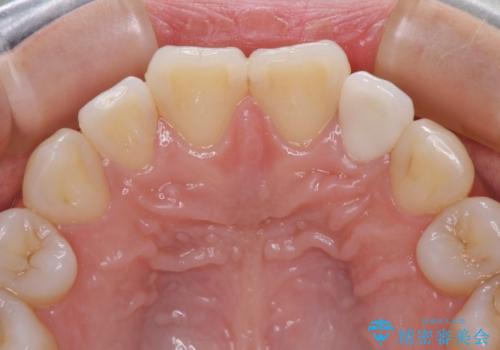

- 前歯に痛みを感じて来院された患者様です。

以前虫歯治療を行った歯が痛み出し、鼻の下を押すと強い痛みを感じていました。

根管治療を行い、その後オールセラミッククラウンにて補綴治療を行うこととしました。